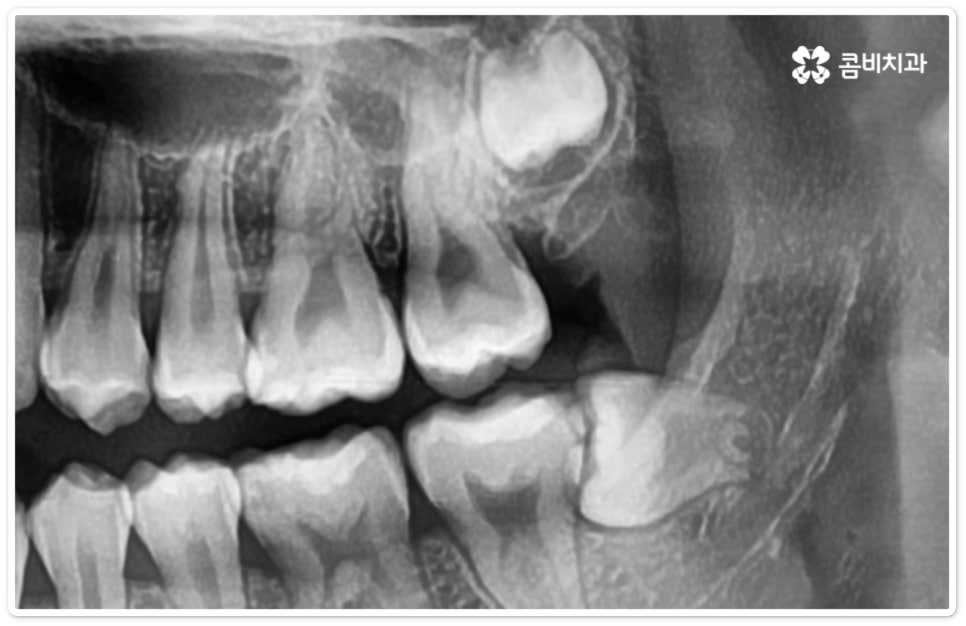

사랑니의 개수, 위치, 각도나 뿌리의 형태, 매복 깊이 등은 사람마다 다른데 그 중에서 특히 완전히 매복된 상태로 비스듬히 누운 채 자리잡은 아래 사랑니의 경우 턱을 가로지르는 하치조 신경과 가깝기 때문에 누운사랑니발치 시 신중을 기하지 않으면 혹시 모를 부작용인 감각 이상을 초래할 수 있으므로 뛰어난 해부학적 지식과 풍부한 임상 경험, 세심한 기술력을 가지고 있는 숙련된 의료진에게 치료를 받으시길 권유드리고 있어요. 혹시라도 신경 손상이 발생하게 되면 입술이나 턱이 마취된 듯 침이 흘러도 감각이 없거나 양치질을 할 때 물이 입술밖으로 세어나가는 상태가 유발될 수 있으니 조심해야 할 거예요.

특히 40세 이상 성인분들의 경우 치아의 긴 뿌리가 완전하게 형성이 되어 있어 치근 유착이 심한 케이스가 있을 수 있으며 대부분 연령이 증가할수록 사랑니 주위 뼈가 단단해지고 탄력성이 감소하는 경향을 보이기 때문에 상황에 따라 무리하게 매복된 뿌리까지 발치할 경우 턱뼈가 부러지거나 신경이 손상되는 등의 합병증 위험이 증가하는 케이스에서는 치아 뿌리는 남긴 채 사랑니의 머리 부분만 잘라서 빼내는 치관절제술을 시행해야 할 수도 있는데요. 이런 경우 약 14%81%는 치관절제술 후 치아 뿌리가 상방으로 움직여서 잇몸 밖으로 노출이 되기 때문에 다시 치근을 제거하는 수술을 해주게 되는데, 환자분들의 입장에서는 수술을 두 번에 걸쳐 하기 때문에 거부감이 들 수 있으나 하치조 신경과의 거리를 벌린 후 완전히 제거하는 것이 통증 및 감염의 위험을 줄이는 보다 안전한 방법이므로 치관절제술 후 1달1년 정도의 시간을 두고 3D CT 촬영을 통해 다시 위치를 꼼꼼하게 확인한 후 치료 받으시길 권유드리고 있어요.

매복 형태의 사랑니는 잇몸을 절개하고 발치해야 하며, 특히 깊숙하게 누운사랑니발치 시에는 신경을 건드리지 않도록 사랑니를 조각내어 조심해서 빼내야 할 뿐 아니라 환자분들의 상태에 따라 잇몸뼈를 조금씩 삭제해야 할 수도 있기 때문에 이러한 고난도 시술에는 주변 조직의 손상을 최소화하고 혹시 모를 부작용의 위험을 줄이며 출혈 및 통증이 커지지 않도록 하기 위해서 시술자의 높은 숙련도가 더욱 요구된다고 할 수 있어요. 또한 매복된 사랑니의 각도, 뿌리 형태, 인접 치아와의 관계, 신경 위치 등을 정확하게 파악하고 체계적인 맞춤 계획을 세워 무리하지 않게 사랑니 발치 수술을 진행하기 위해서 정밀 진단이 가능한 3D CT 장비가 있는 치과에서 꼼꼼한 검사부터 받아보는 것이 중요할 거예요.